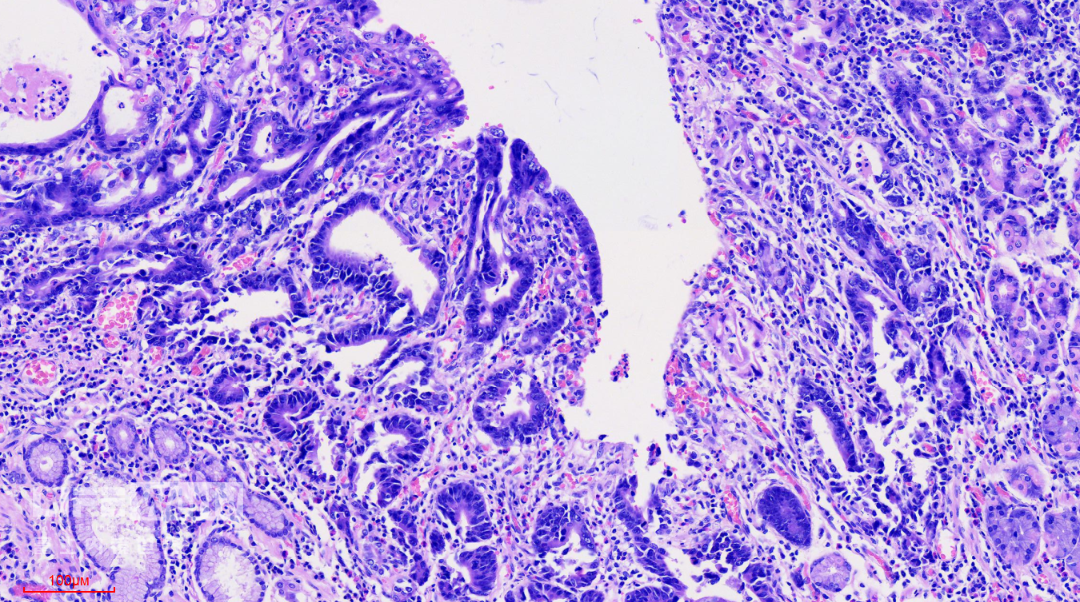

HE染色:2号切片示中分化腺癌,6号切片示高级别上皮内瘤变,局灶癌变。

这是2号切片,病变位于一条皱襞顶端。

病变处(红圈内)可见不规则的腺管状结构,部分呈筛网状。图中可以看出,病灶间可见相对正常的胃底腺结构。图片中最深的病灶已经侵及粘膜肌层。

病变处细胞异型性明显。病变内部可见多处扩张的腺管,内部可见坏死碎片。对应胃镜图片上的白色球状物。